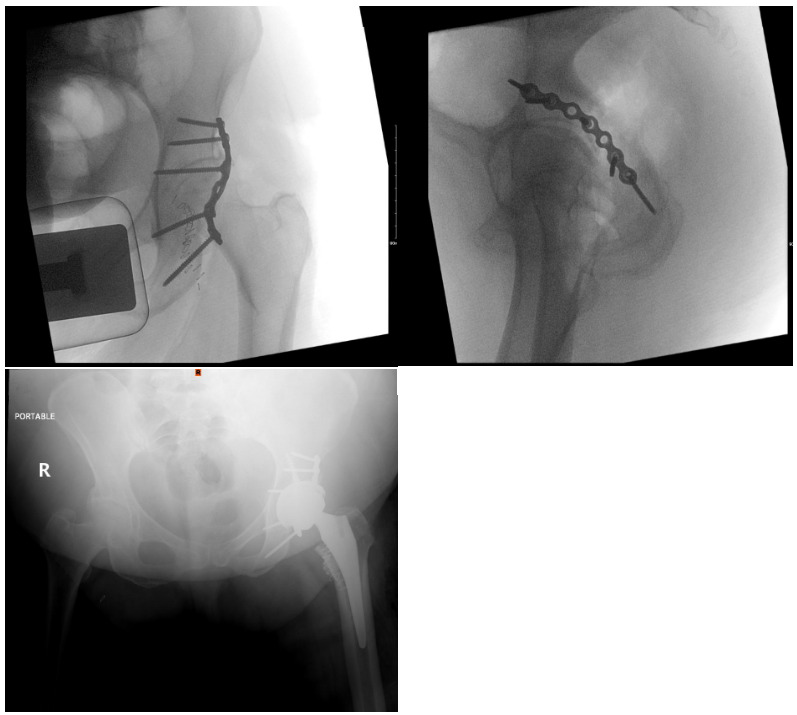

A 64-year-old female with diabetes, hypertension, and dyslipidemia was involved in a motor vehicle accident, resulting in significant injuries. She presented to the Emergency Department via Medivac and underwent a comprehensive trauma assessment. Orthopedic evaluations reveal a fractures dislocation of the left acetabulum with a posterior wall fracture and a femoral head fracture (Figure 1. Figure 2, Figure 3). Additionally, a minimally displaced fractures of the left tibial plafond was identified. Due to the complexity of her injuries and considering her age, a surgical plan was formulated for fixations of the acetabular and femoral head fractures, along with total hip replacements on the left side, and fixations of the tibial plafond fractures. After induction of general anesthesia and regional block, the patient was positioned in lateral decubitus for the hip procedures. Utilizing the Kocher-Langenbeck approach, the posterior wall fracture was stabilized with lag screws and a buttress plate (Figure 4A, 4B). The hip was then dislocated, the femoral neck cut, and the acetabulum reamed. A Stryker Trident cup size 46 was inserted for a press-fit, augmented with three screws, and a metal liner for dual mobility was added. Subsequently, the femur was broached, and an Accolade stem size 2 with a double head was implanted, ensuring excellent stability and appropriate legs length (Figure 4C). The operation concluded with thorough irrigation and closure in layers. The patient was then repositioned supine to address the tibial plafond fracture, which was stabilized with a single medial plate, followed by application of a dry dressing and a below-knee backslabs. Postoperatively, the patient experienced mild pain but was otherwise stable. Dressings on the left hip and ankle were intact, with ankle motion preserved and a palpable dorsalis pedis pulse. She began mobilization with physiotherapy from day one and showed no active complaints throughout her recovery, proceeding smoothly until discharge (Figure 5).